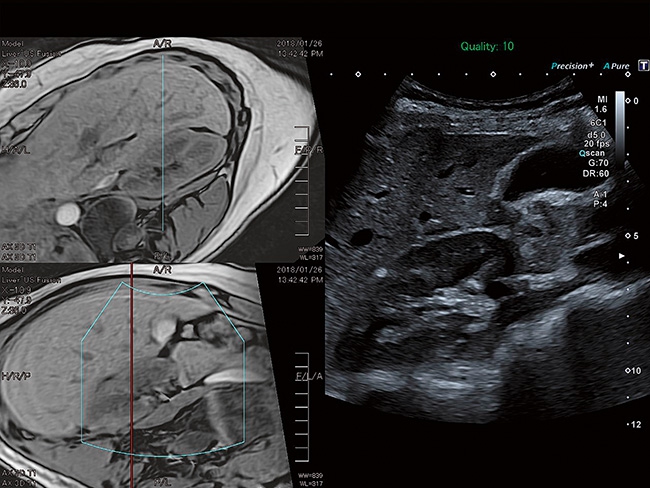

Aplio a550 – это многофункциональная УЗИ система экспертного класса. Высокое качество изображения и интуитивно понятный интерфейс поможет вам обеспечить высокую производительность и скорость проведения исследования. Совершенные технологии визуализации помогают повысить диагностическую уверенность даже в сложных случаях.

Стационарная цифровая ультразвуковая система Toshiba (Canon) a550. Современные технологии визуализации, цифровое формирование луча, удобная для работы панель. Характеристики, удовлетворяющие требованиям к системам УЗИ экспертного класса.

Aplio a550 может работать с линейным матричным датчиком и поддерживает новейшие монокристаллические датчики. Также Aplio a550 поддерживает большое количество дополнительных опций, таких как - SMI, Компрессионная эластография, Эластография сдвижной волны, Smart Fusion, исследования с использованием контраста (CEUS), 3D реконструкции в реальном времени (4D), функции автоматической оценки подвижности миокарда и фракции выброса.